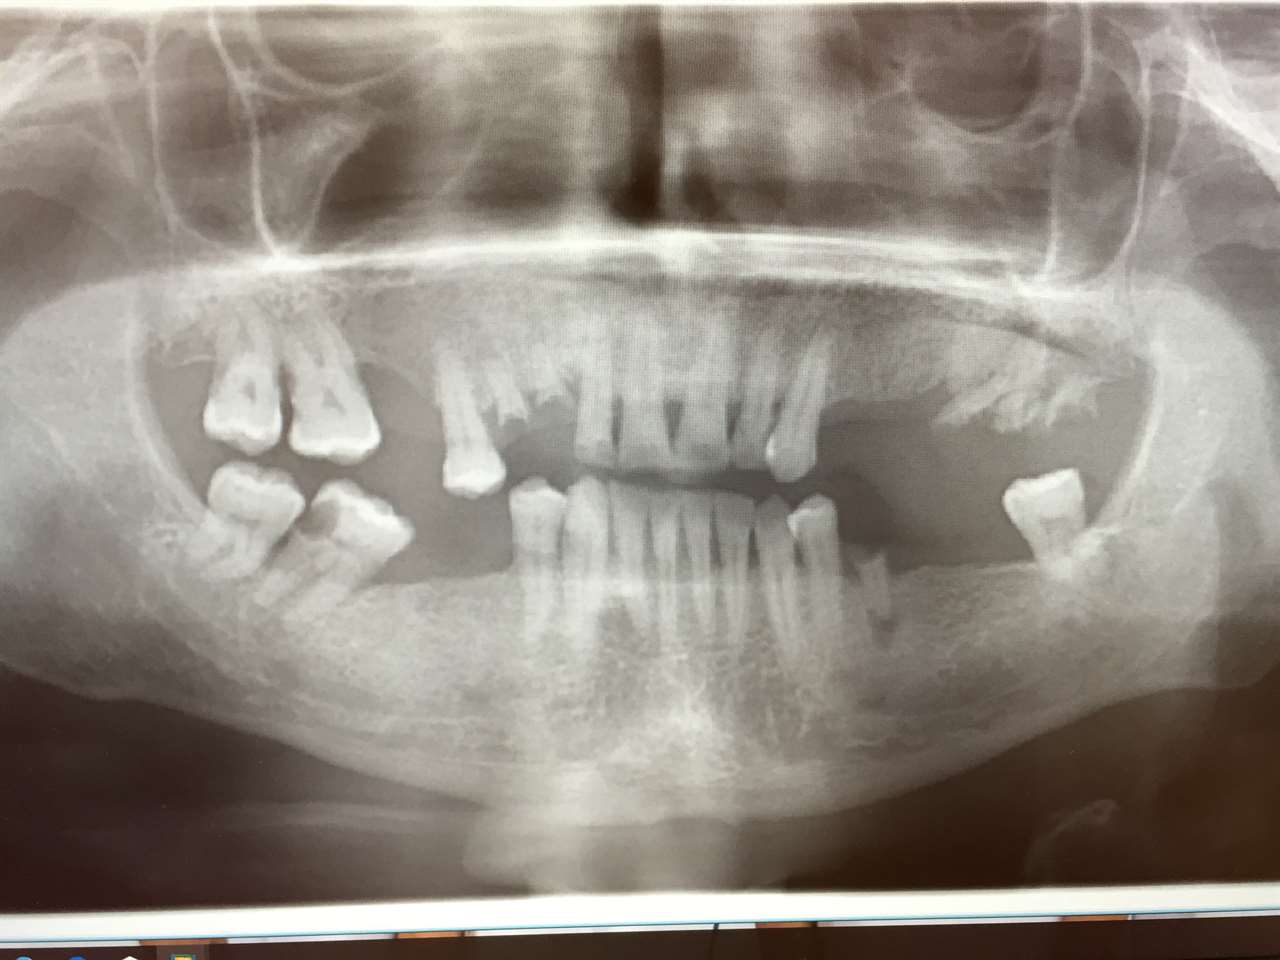

Alsó állcsont teljes rehabilitációja 72 óra alatt, azonnal terhelhető implantátumokkal súlyos paradontitisben szenvedő dohányzó páciens esetében. Az alsó állcsont fogai mind mozogtak az előrehaladott fogágypusztulás miatt.

A fogakat eltávolítottuk, a gyulladt, fertőzött csontot kitakarítottuk, kifertőtlenítettük, majd azonnal implantáltunk.

Svájci, IHDE márkájú, azonnal terhelhető implantátumokat helyzetünk be, és ezekre harmadnapra rögzített, hosszútávú, fémvázas, esztétikus műanyaggal leplezett hidat ragasztottunk be.

Ezt az ideiglenes hidat a sebek gyógyulása miatt használjuk, de tartóssága miatt véglegesként is használható. A legtöbb esetben, ahogy itt is, 6 hónap múlva porcelán hídra cseréljük, a teljes gyógyulás után.